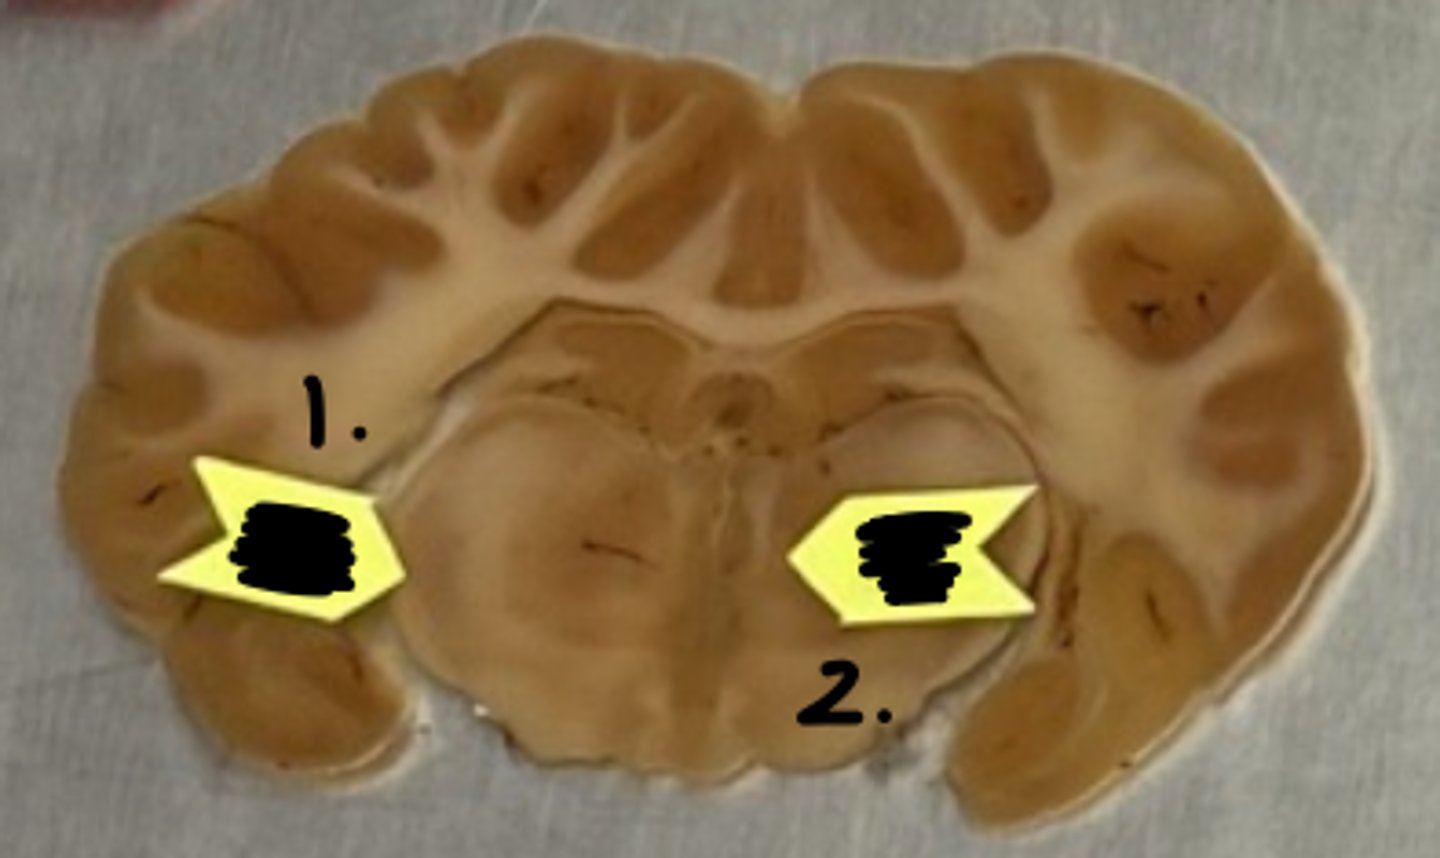

optic tract

what structure is labeled as #1 ?

optic chiasm